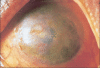

Ocular herpes simplex virus (HSV) infection remains a major cause of corneal blindness. Several topical and oral antiviral medications have been used to treat herpetic keratitis. Advances in topical ophthalmic antivirals have been made over the past several decades. The first antivirals that were discovered were cytotoxic, while the antivirals developed more recently, such as acyclovir and ganciclovir, have exceeded these drugs in both efficacy and tolerability. Commercially available outside of the US since 1996, ganciclovir ophthalmic gel, 0.15% (GCV 0.15%, European tradename: Virgan((R))) is sold in more than 30 countries and has become the standard of care in treating acute herpetic keratitis. GCV 0.15% has been studied in animal models of ocular herpes, in healthy volunteers, and in several clinical studies. It has been found to be safe and effective at treating acute superficial herpetic keratitis. Previous preclinical studies of ganciclovir have shown activity against several common adenovirus strains and one recent clinical study demonstrated clinical effect against adenoviral conjunctivitis. This review is intended to provide a comprehensive overview of the GCV 0.15%, including a brief summary of the etiology and available treatments for ocular HSV, an explanation of GCV 0.15% mechanism of action, a compendium of preclinical and clinical GCV 0.15% studies, and an introduction into new areas of interest involving this drug.